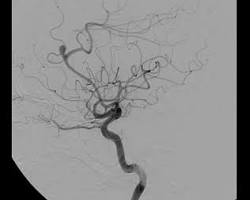

• 뇌혈관 조영술: 혈관 좁아짐 정도 확인

• 뇌혈관 조영술 이미지